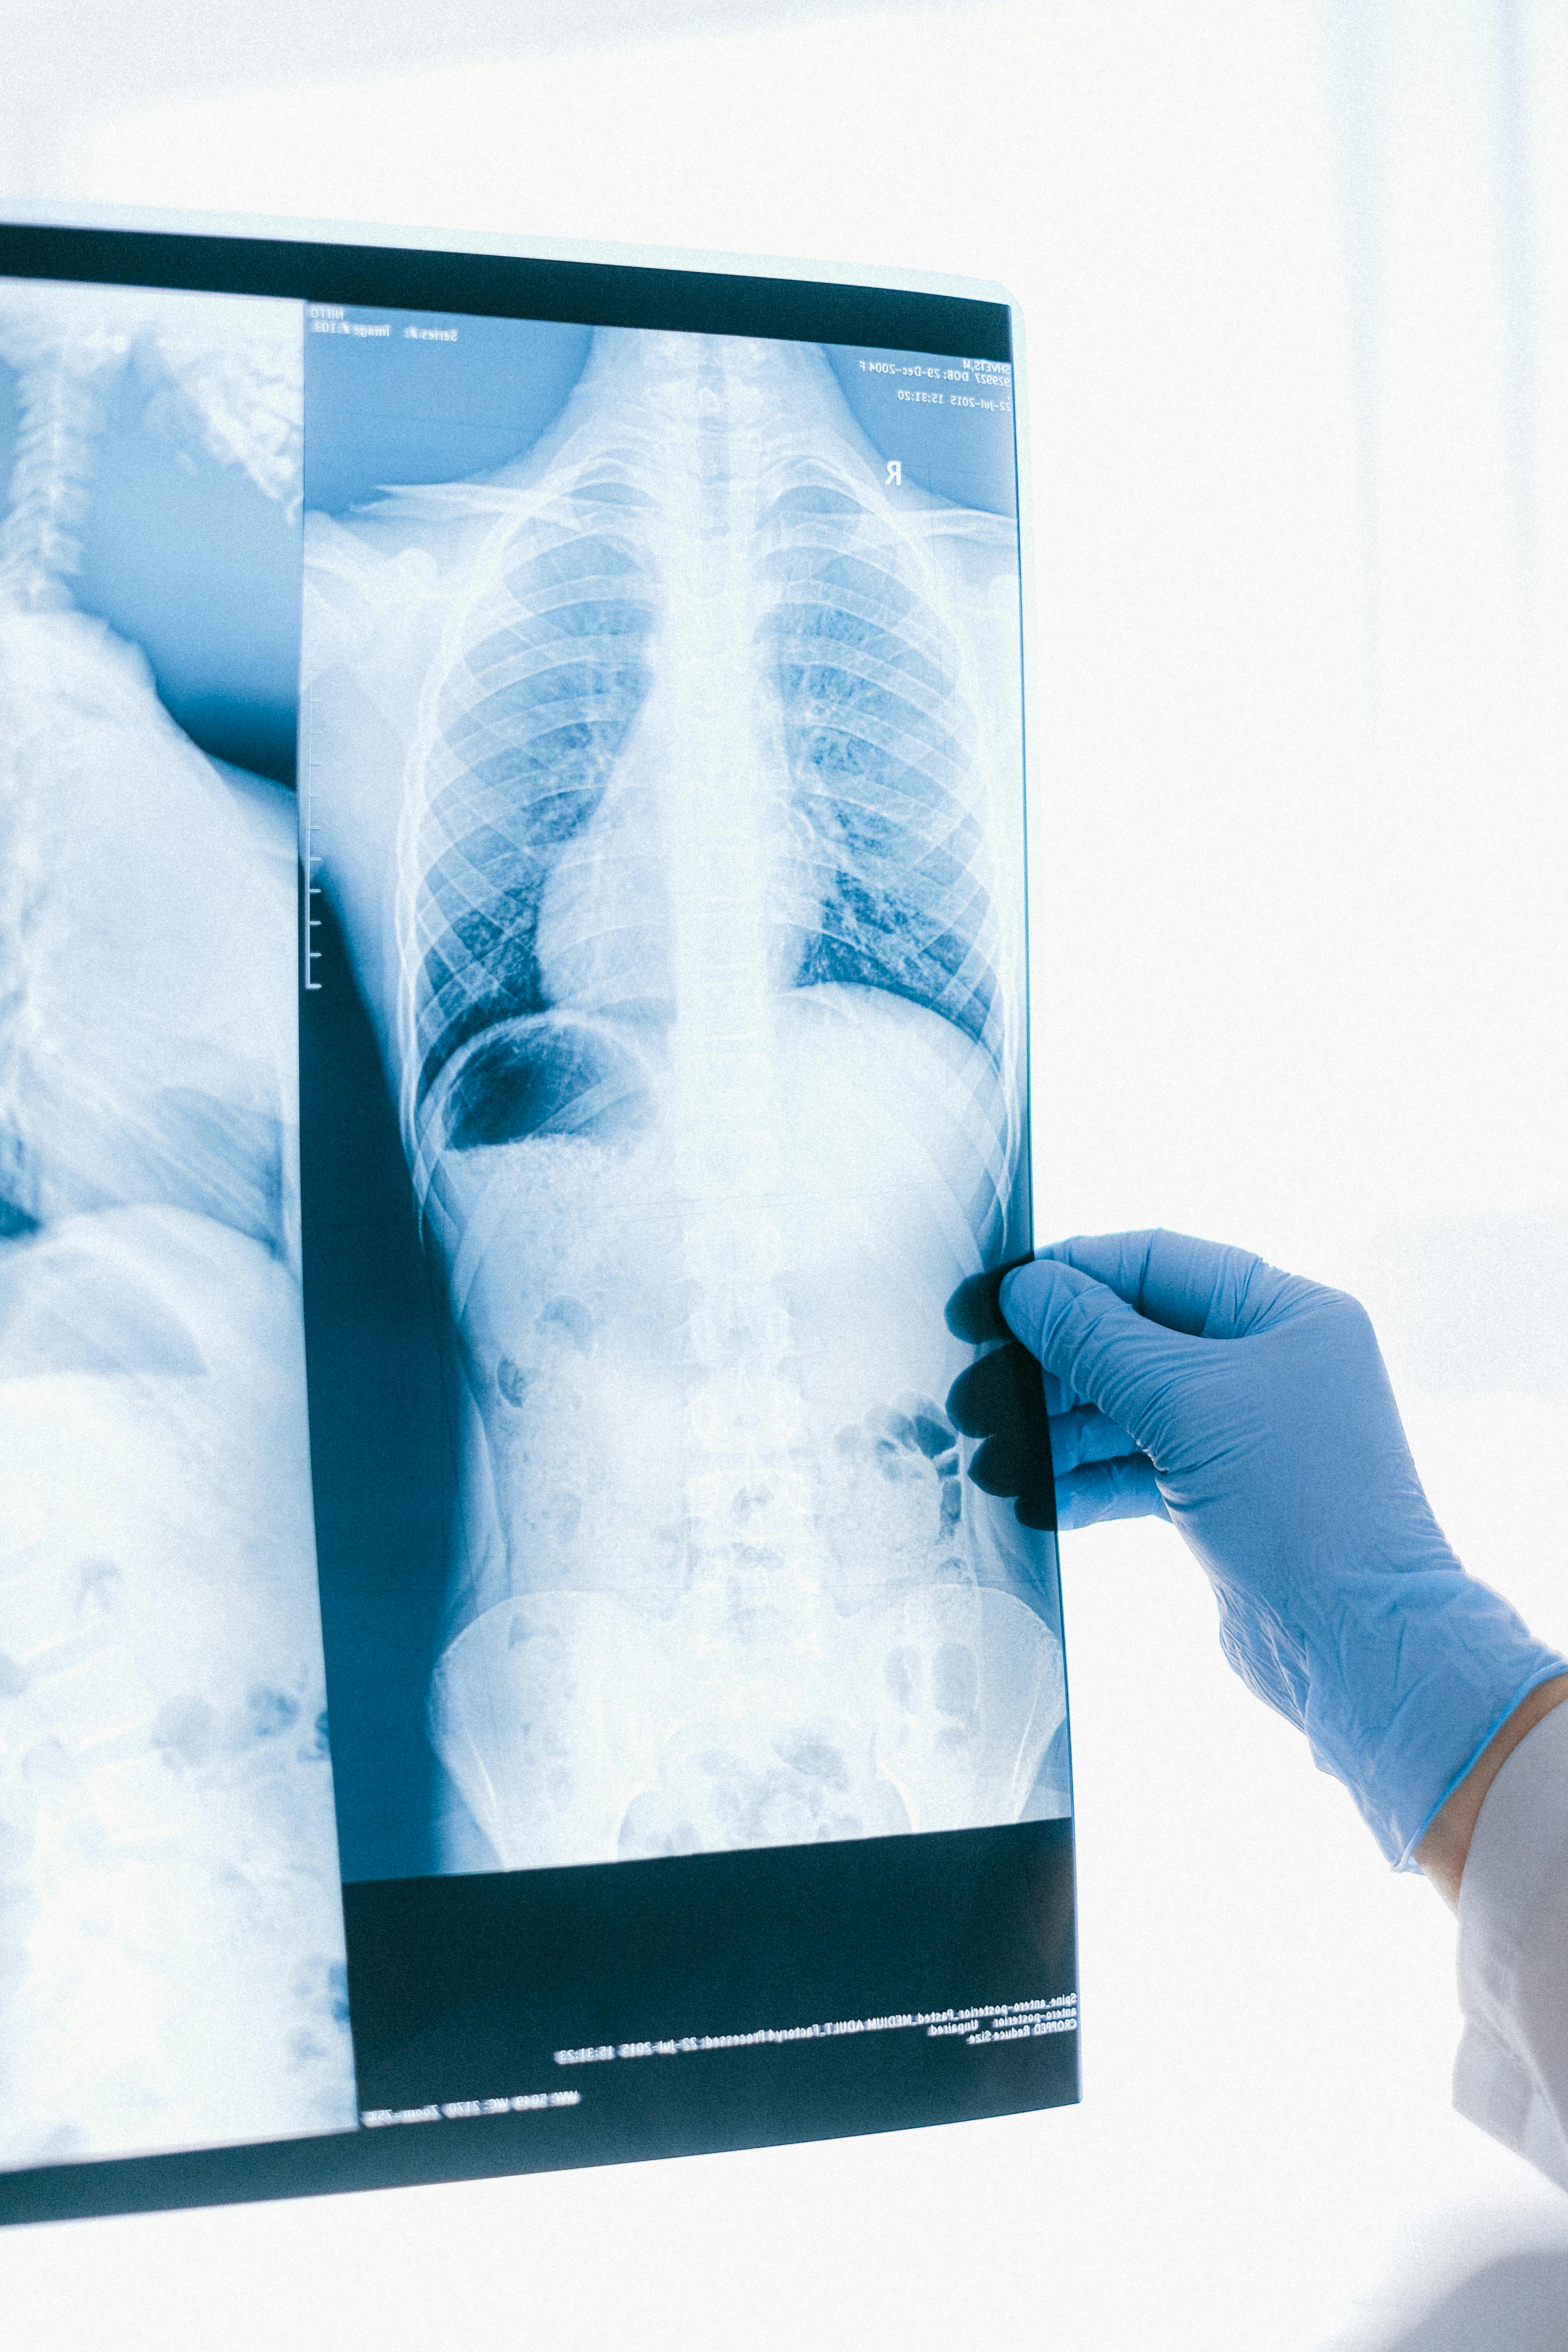

- 흉부 X선: 폐렴이 진행된 경우 폐의 염증 상태를 확인할 수 있습니다.